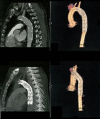

Background: We report a case of delayed endovascular correction of graft collapse occurred after emergent Thoracic Endovascular Aortic Repair (TEVAR) for traumatic aortic isthmus rupture.

Case presentation: In 7th post-operative day after emergent TEVAR for traumatic aortic isthmus rupture (Gore TAG® 28-150), a partial collapse of the endoprosthesis at the descending tract occurred, with no signs of visceral ischemia. Considering patient's clinical conditions, the graft collapse wasn't treated at that time. When general conditions allowed reintervention, the patient refused any new treatment, so he was discharged.Four months later the patient complained of severe gluteal and sural claudication, erectile disfunction and abdominal angina; endovascular correction was performed. At 18 months the graft was still patent.

Discussion and conclusion: Graft collapse after TEVAR is a rare event, which should be detected and treated as soon as possible. Delayed correction of this complication can be lethal due to the risk of visceral ischemia and limbs loss.